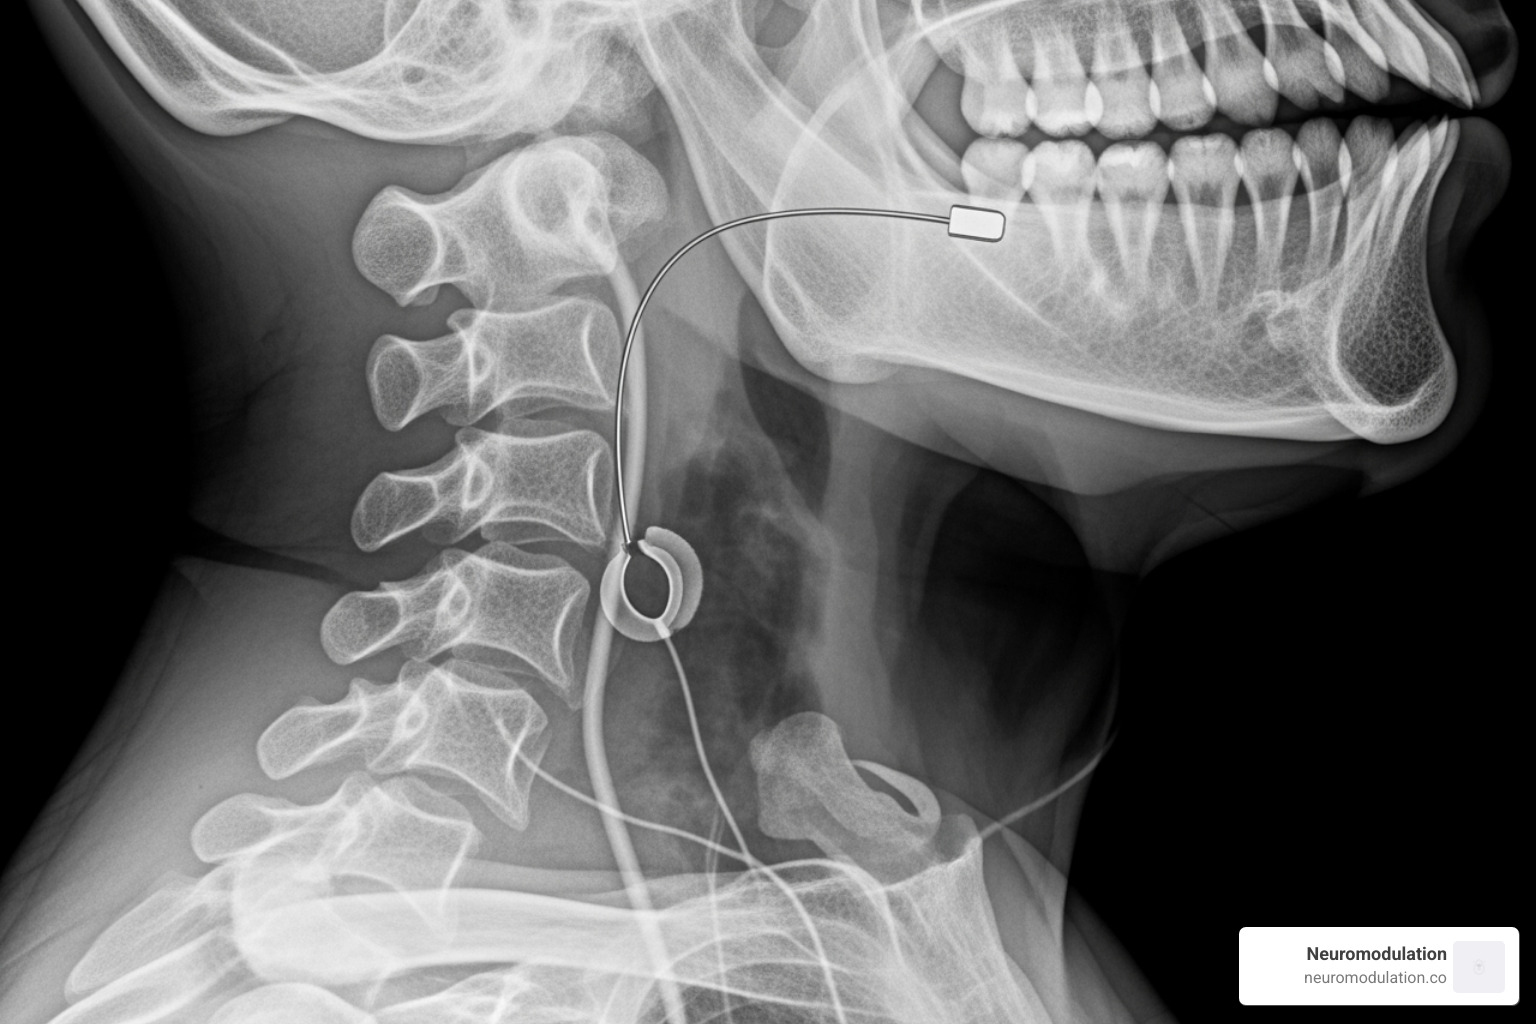

While your chest X-ray shows two-thirds of the story, we need a separate neck X-ray to see the third critical piece: the stimulation lead that actually treats your sleep apnea.

Your neck radiograph reveals this fine wire extending upward from your chest device, traveling under your skin like a hidden highway, until it reaches its destination in the area under your chin called the submandibular region.

The magic happens at the end of this lead – a tiny cuff electrode that your surgeon carefully wrapped around a branch of your hypoglossal nerve. This is the twelfth cranial nerve, and it controls all the muscles that move your tongue.

On your lateral neck X-ray, we can trace this lead’s path and make sure it follows a smooth, natural curve without any sharp bends or kinks. The cuff itself might appear as a small bright spot encircling the nerve, though sometimes it’s quite subtle.

Here’s where the real treatment occurs: when that cuff delivers its gentle electrical pulse, it activates your genioglossus muscle – the main muscle responsible for pushing your tongue forward. This forward movement opens your airway, preventing the collapse that causes your sleep apnea episodes.

Your radiologist examines the soft tissue landmarks around the lead to confirm it’s positioned for optimal nerve stimulation. This detailed view of hypoglossal nerve stimulator radiology ensures your device is ready to deliver years of effective therapy, helping you breathe easily and sleep soundly every night.